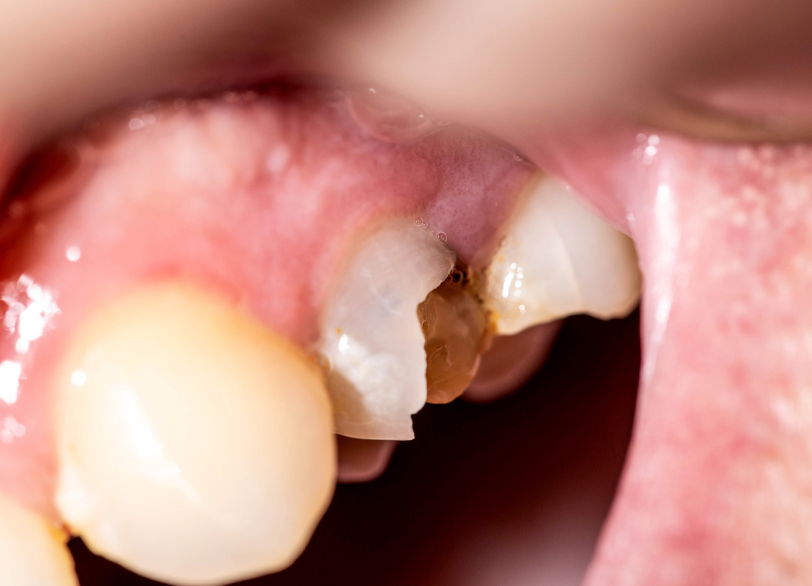

むし歯

親知らずは一番奥にあるため歯ブラシが届きにくく、非常にむし歯になりやすい歯です。

問題は親知らず自身だけでなく、その手前にある健康な歯(第二大臼歯)までむし歯にしてしまうリスクが高いことです。

手前の歯は将来にわたって長く機能すべき大切な歯です。

その歯を守るために、親知らずの抜歯が必要となることがあります。